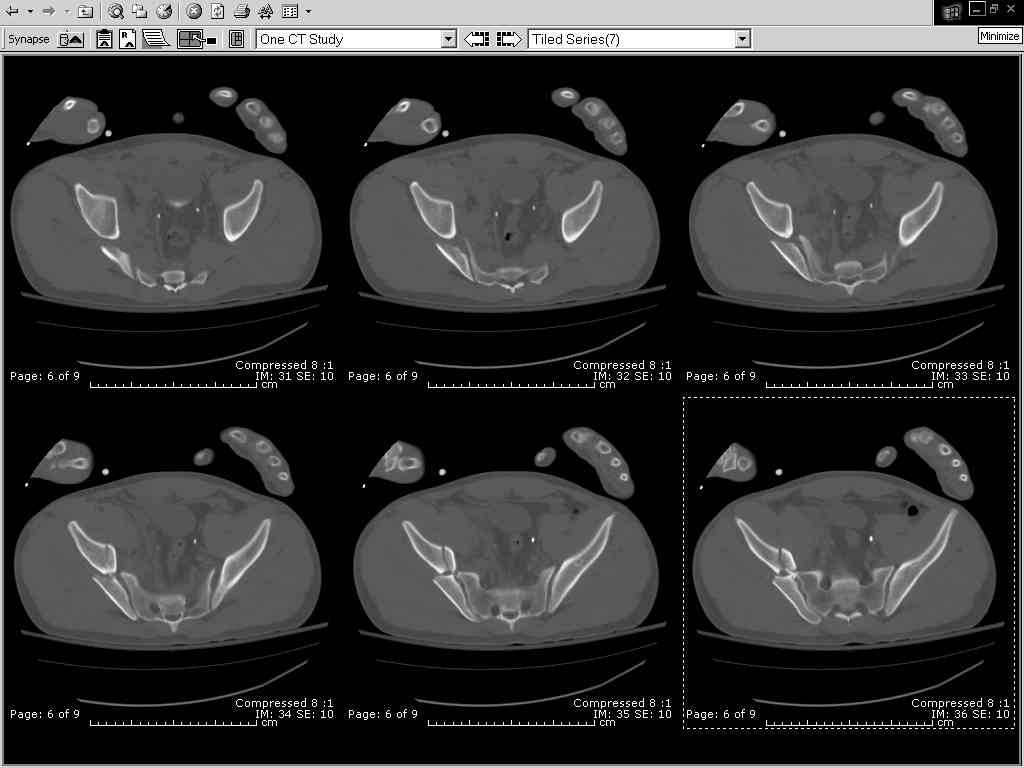

Here are the postop fluoros.

First exposed symphysis & clamped w/Faraboeuf as close to anatomic as possible.

Then extended to R ilioinguinal,really just the lateral window.

Reduced the triangular wedge piece of iliac wing to posterior intact ilium (crescent), held w/k-wire, then used 3-hole push plate to keep from moving, lagged from lat-med w 3.5 screw.

Then 6-hole plate along brim with 1 screw in R sacral ala. Then lagged 2 screws along crest A --> P. finally 10-hole plate along inner aspect of crest. R posterior ilium still a bit stepped off.

Symphysis then 'fine-tuned' & reduced as close as possible to anatomic (but, still with forward rotation of R hemipelvis - or, is it extension?) Accepted that amount of deformity and plated symph

with 4-hole symphyseal plate.

Fluoroed L SI joint and it seemed stable, but wide. So, applied c-clamp to try to squeeze down L SI joint (and note, on the last slide attached, that it's still wide), and got it closer. Single perc Iliosacral screw 40mm thread.

Applied second plate anteriorly on symphysis as I wasn't confident L SI was as stable as it could be and wanted to protect it better.